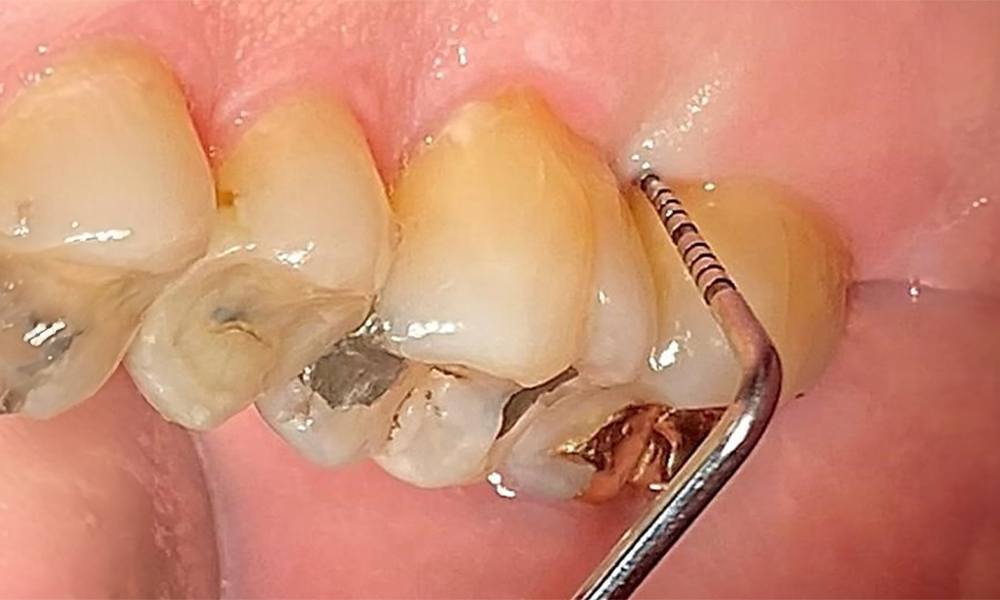

Supragingival and subgingival biofilm removal is indispensable for maintaining the stability of the periodontal condition. Air polishing using low-abrasive powder is suitable for this purpose. Periodontal pockets and exposed root surfaces must be cleaned with low-abrasion powders. The use of a flexible parotip is recommended for patients with increased probing depths (deeper than 5 mm) (Fig. 10). (9)

Subgingival application of the flexible air polisher tip (Proxeo Aura, W&H, shown here) to the mesiopalatal aspect of tooth 27 with a periodontal pocket depth of 5 mm. © Dr R. Krapf

Fig. 10: Subgingival application of the flexible air polisher tip (Proxeo Aura, W&H, shown here) to the mesiopalatal aspect of tooth 27 with a periodontal pocket depth of 5 mm. © Dr R. Krapf